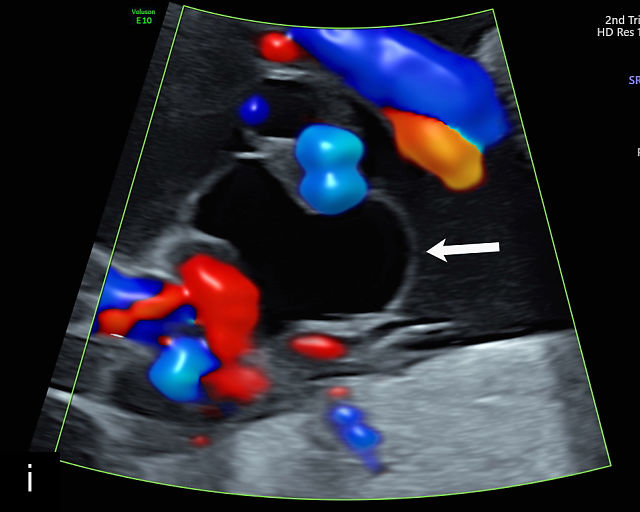

There are three types of vasa previa.30,262 In Type 1, the cord inserts into the membranes rather than the placenta. Unprotected vessels then traverse the membranes over the cervix to insert into the placenta (Figure 21a; Video 12). In Type 2, unprotected vessels running through the membranes over the cervix connect the main placental lobe with an accessory lobe (Figure 21b).263 In Type 3, there is generally a normal placental cord insertion, and unprotected vessels exit one placental edge, run through the membranes over the cervix and then boomerang to insert into the placental edge at another site (Figure 21c).25,28,29,264 Regardless of the type, all these expose the fetus to the same risks.

21